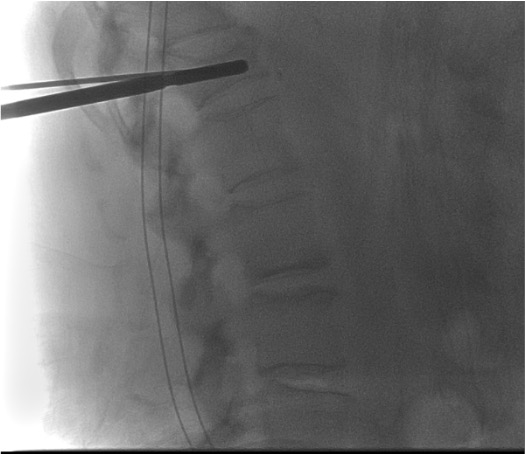

- Working cannula (implant-specific trocar) advanced to posterior one-third of vertebral body โ confirmed on lateral fluoroscopy

- After working cannula placed at posterior one-third of vertebral body: inner trocar replaced with guidewire, then bone drill (reamer)

- Drill advances to desired implant position โ terminates just short of the anterior vertebral body cortex

Bilateral pedicle entry โ working cannulae

Guidewire and bone drill (reamer)